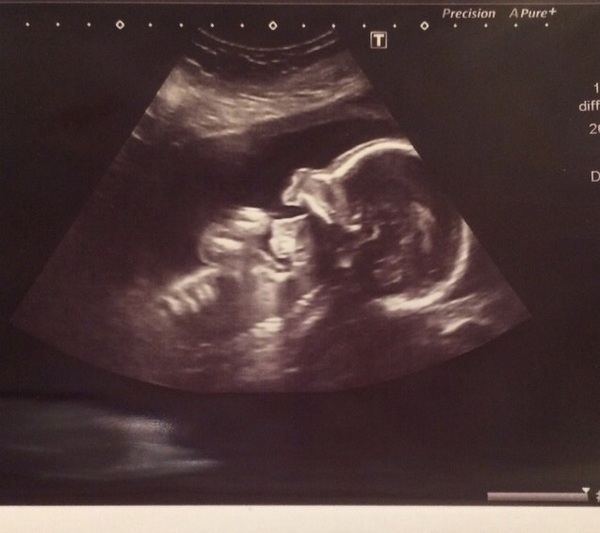

20+2 and scan went really well. Everything looking as it should! Such a relief! It kept opening its mouth to put its hands in and she got a brilliant pic...

Lucie that's a great happy picture! Congrats on your scans to you and crazyzoo.